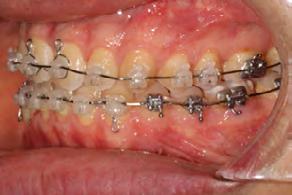

Approximately six months after insertion of the RPE, digital scans were taken for SureSmile custom wires and the patient was scheduled for the SFOT procedure with the oral surgeon. The RPE was removed, SureSmile wires inserted and segmental corticotomies performed, immediately followed by further vertical elastics on the right side (Figure

4). Archwires were upgraded incrementally into 19 x 25 SS. Once the bite was completely closed, the patient was referred to the myofunctional therapist to begin treatment. Eight sessions of myofunctional exercises were performed, focusing on muscle building, toning, synchronicity and awareness. Improvement in correct chewing, swallowing and resting postures of the lip and tongue were addressed. All appliances were removed 21 months after initial insertion (Figure 5), and the patient was referred to a re-

Figure 4. Post-corticotomy, with SureSmile custom wires.